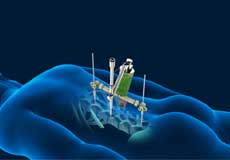

Sacroiliac Joint Minimally Invasive Fusion

Sacroiliac (SI) joints are joints in the lower back region, where the sacrum and ilium bones join. Although these joints are small and have limited motion, they play an important role in connecting your spine to the pelvic bone and lower part of your body. They perform an important function in absorbing shock from the upper portion of your body.

Minimally Invasive TLIF

Transforaminal lumbar interbody fusion (TLIF) is a minimally invasive fusion of the vertebrae of the lumbar region (lower back). It is designed to provide stability to the spine and treat back and leg pain.